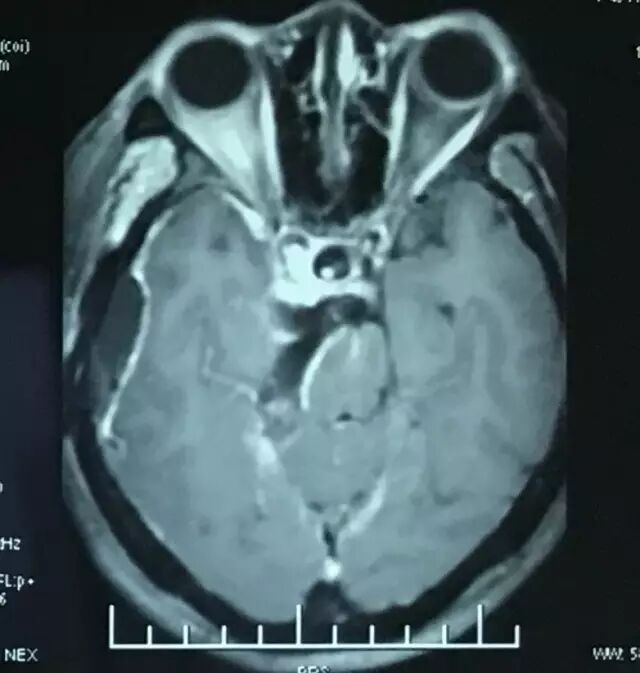

术后头颅CT扫描。

术后MRI T1平扫,复查可见明胶海绵影(高信号)。

术后MRI增强核磁扫描